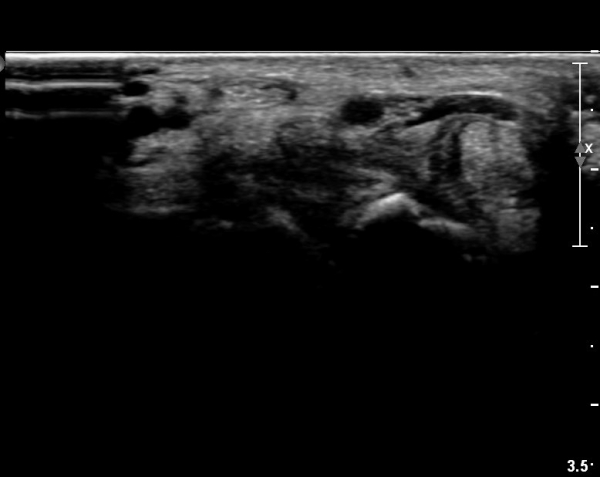

µÎµ¢±ÙÀ°À» Áö¹èÇÏ´Â ¸»´Ü Á¤Áß½Å°æ °¡Áö º´Áõ ¼Ò°ßÀ» º¸¿© ÀÓ»óÀûÀ¸·Î ¼öÀåºÎ¿¡¼­

Á¾¾ç¿¡ ÀÇÇÑ Á¤Á߽Ű渻´Ü°¡ÁöÀÇ ¾Ð¹ÚÀÌ ÃßÁ¤µÇ¾úÀ¸³ª  ÃÊÀ½ÆÄ°Ë»ç»ó ¼Õ¸ñºÎÀ§¿¡¼­ Á¤Á߽Ű泻

Àú¿¡ÄÚ Á¾¾çÀÌ °üÂûµÇ°í Àú¿¡ÄÚ Á¾¾çÀÇ ½Å°æ³» À§Ä¡°¡ Âü°í¹®Çå¿¡¼­ º¸°íÇÑ ¹Ù¿Í °°ÀÌ

Á¤Á߽Ű泻¿¡¼­ µÎµ¢±ÙÀ°À» Áö¹èÇÏ´Â ¿îµ¿½Å°æÀÇ À§Ä¡¿Í ÀÏÄ¡ÇÏ¿© Á¤Á߽ŰæÁß¿¡¼­ µÎµ¢±ÙÀ°À»

Áö¹èÇÏ´Â ½Å°æ µ¢¾î¸®(fascicle)ÀÇ ½Å°æÁ¾À¸·Î ÃßÁ¤ÀÌ °¡´ÉÇϸç ÀÓ»óÀû ¼Ò°ß°úµµ ÀÏÄ¡ÇÑ´Ù.